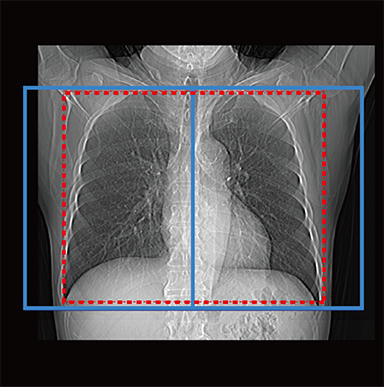

FCT iStream automatically*2 sets the scanning range using the scanogram image by AutoPose function. Since the margins can be set in advance, the range can be customized according to the preference of the facility. iTilt automatically creates and enables observation of tilted images during scanning.

chest

Red: automatically set position, Blue: automatically set position + margin setting position